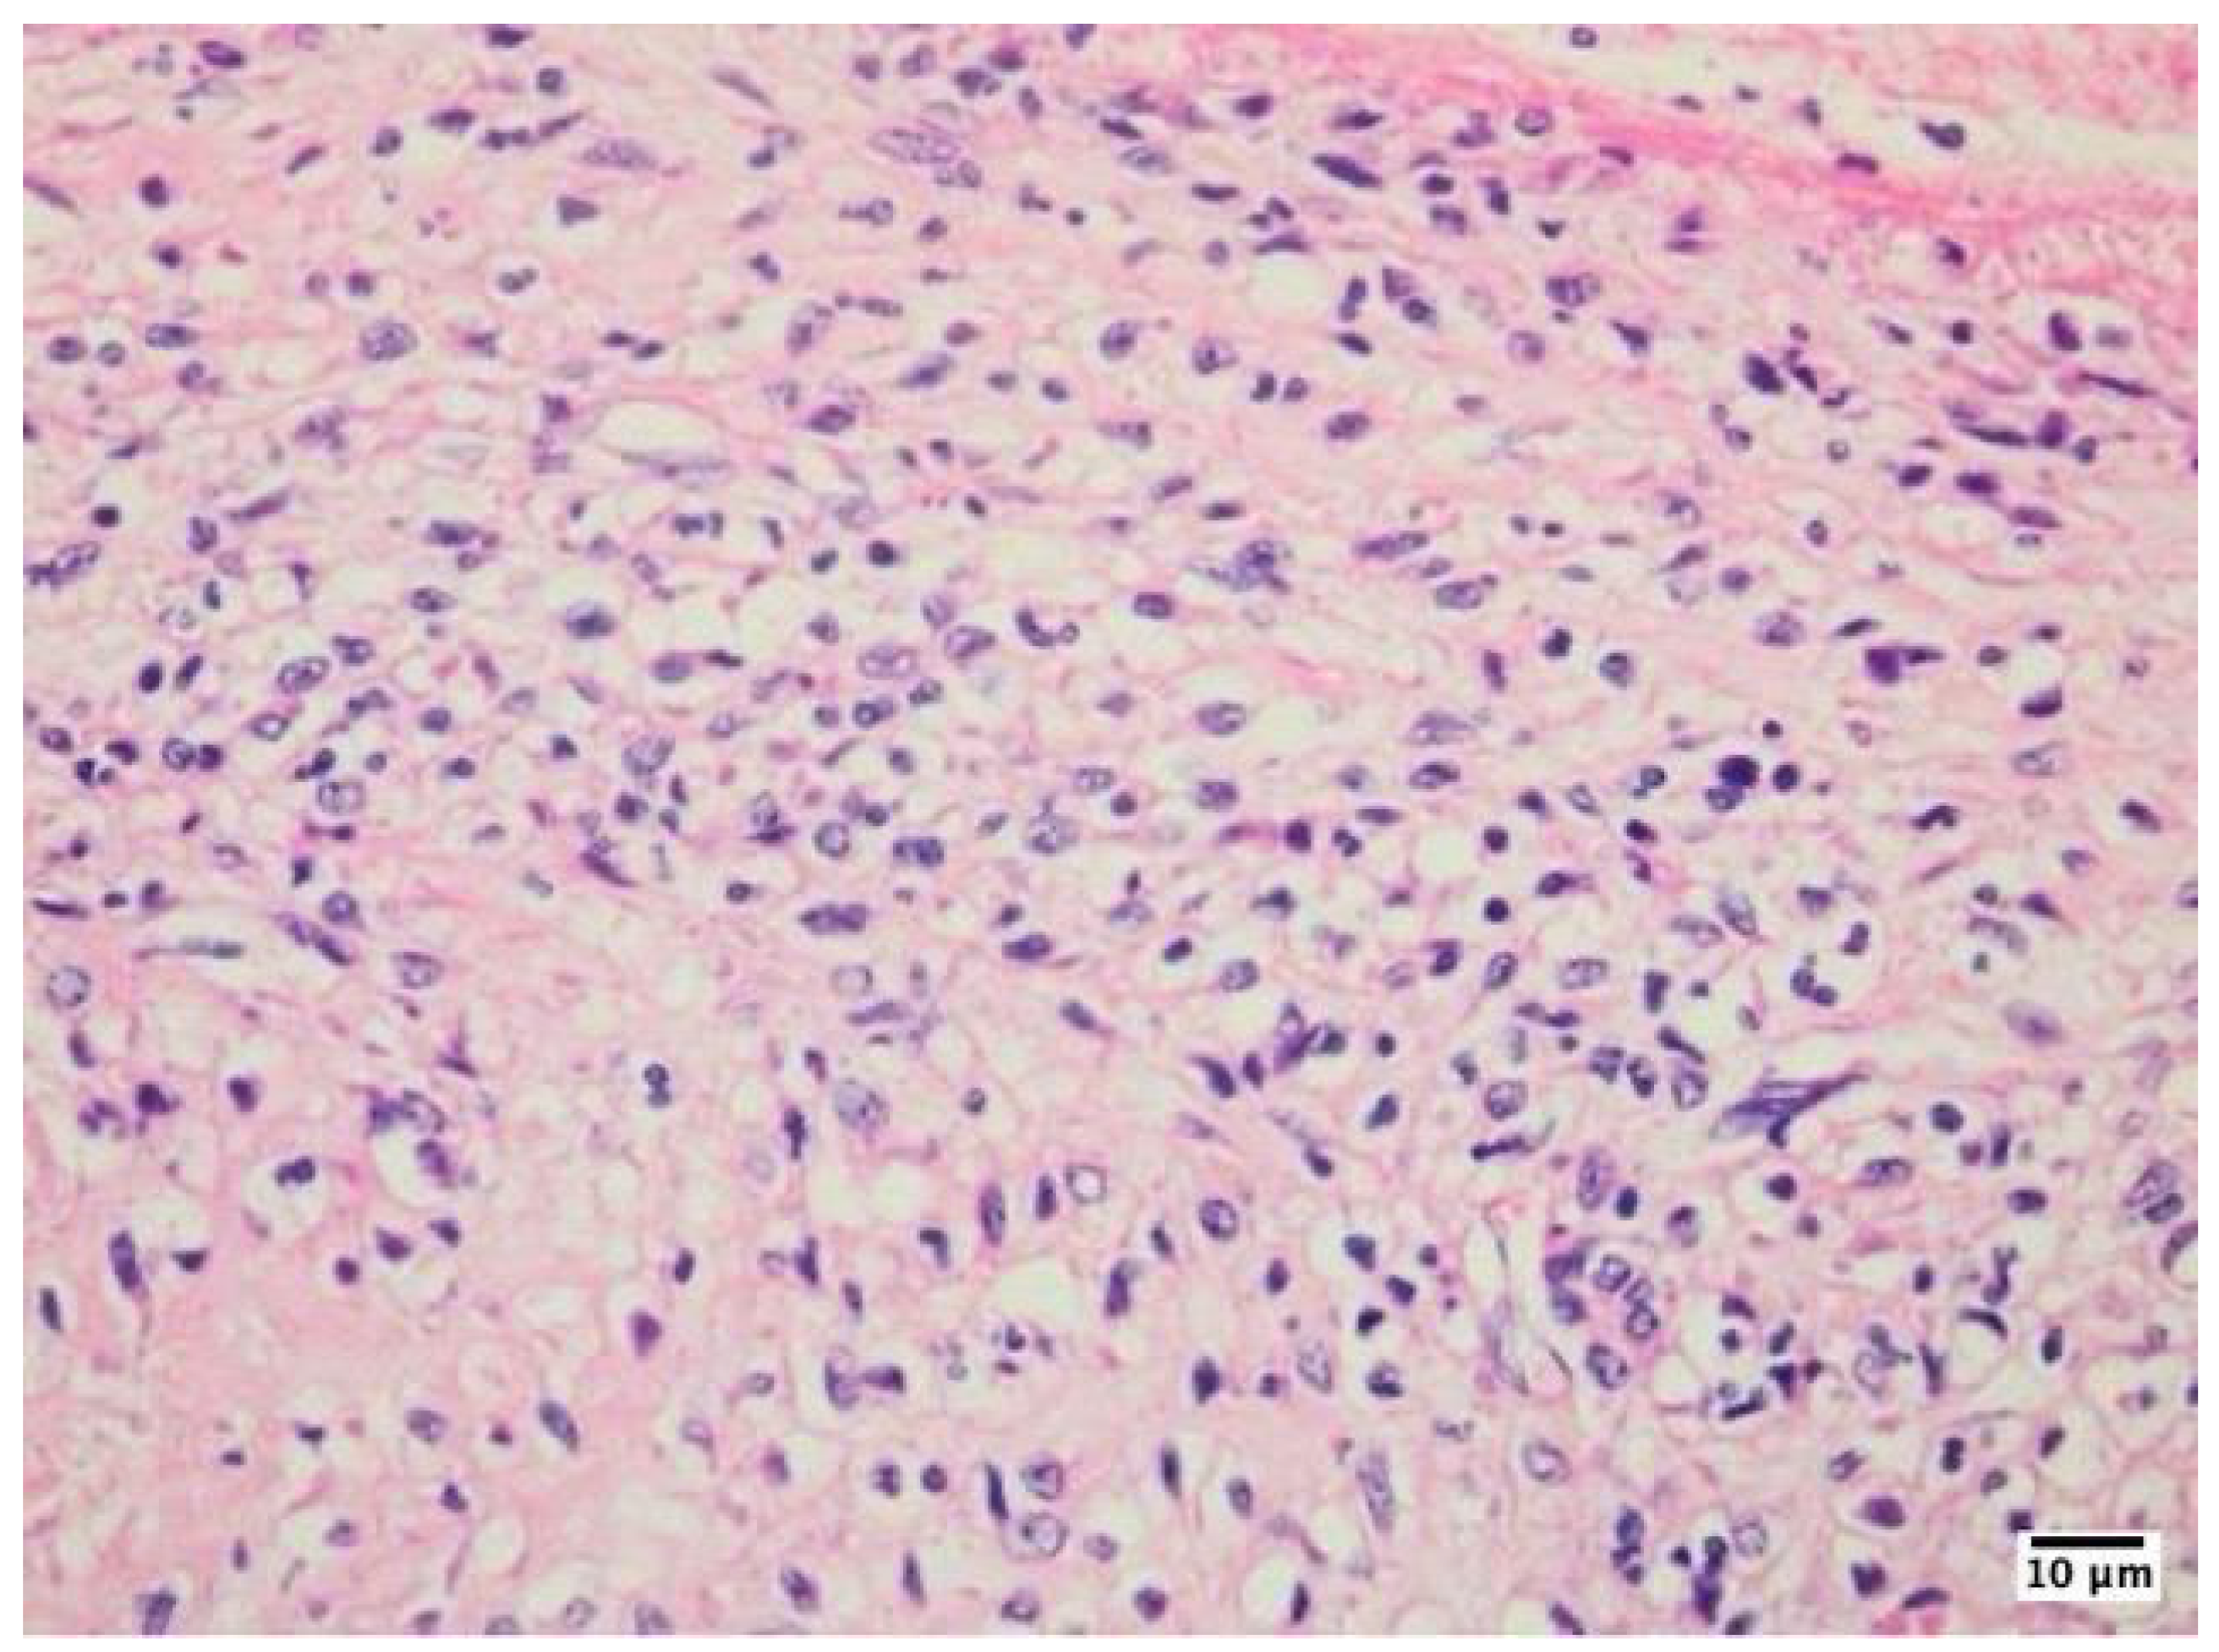

The study revealed distinct histopathological characteristics between IE and non-infective valve dysfunction. The majority of IE cases (87.8%) showed significant inflammatory infiltrates, primarily composed of neutrophils, indicating an active infection. The infective process was predominantly localized to the vegetation on the valve cusp surface, with minimal involvement of the underlying valve tissues. Microorganisms were visually identified in approximately half of the infective endocarditis samples using special staining techniques (Figure 1).

The inflammatory infiltrates in non-IE cases consisted mainly of macrophages and lymphocytes, suggesting a chronic inflammatory process rather than an acute infection (Figure 2, Figure 3, Figure 4).

Figure 2. Histological examination of a mechanical heart valve tissue specimen in mitral position, showed non-infective inflammatory degenerative lesions, as visualized using hematoxylin-eosin staining at 400x magnification with an Olympus BX43 microscope and XC30 camera. This finding is characterized by the presence of numerous macrophages lining the area surrounding the mechanical valve. The accumulation of these immune cells suggests an ongoing inflammatory process, which may be a response to the presence of the artificial valve or a result of chronic tissue irritation.